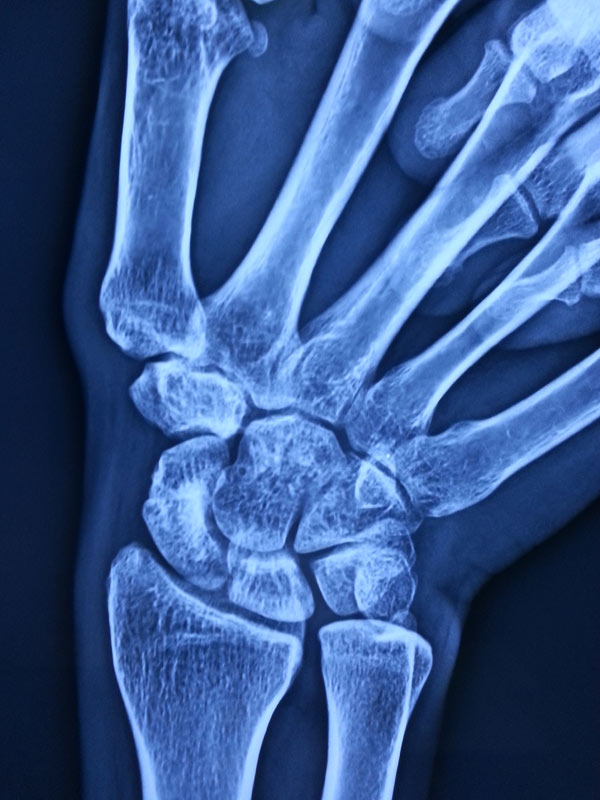

3 months post surgery, patients Scaphoid was totally united and he is able to do all activities with his Rt Hand.

After Surgery